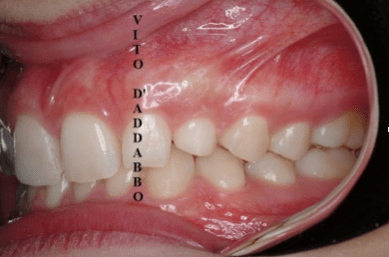

Non di rado accade che manchi in arcata il canino permanente superiore. Questo può essere dovuto a mancanza di spazio ma anche a problemi di eruzione del dente che si colloca lontano dalla propria sede. Nel caso di questa paziente, che presentava anche un grave morso coperto, il canino era dislocato palatalmente e molto distante dalla propria sede. Previo un piccolo intervento chirurgico è stato agganciato e portato in arcata.

prima